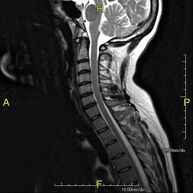

- Cervical spine MRI

This non-invasive diagnostic procedure uses an electromagnetic field and radio waves (from a transmitter and receiver) to acquire high-definition anatomical images of the cervical spine. It is a radiation-free procedure. Indicated for: trauma, spinal degeneration, hernias.

- Thoracic spine MRI

This non-invasive diagnostic procedure uses an electromagnetic field and radio waves (from a transmitter and receiver) to acquire high-definition anatomical images of the thoracic spine. It is a radiation-free procedure. Indicated for: trauma, degenerative problems, hernias, tumours.

- Lumbar spine MRI

This non-invasive diagnostic procedure uses an electromagnetic field and radio waves (from a transmitter and receiver) to acquire high-definition anatomical images of the lumbar and sacral regions. It is a radiation-free procedure. Indicated for: trauma, sciatica, herniated discs, tumours, infections.